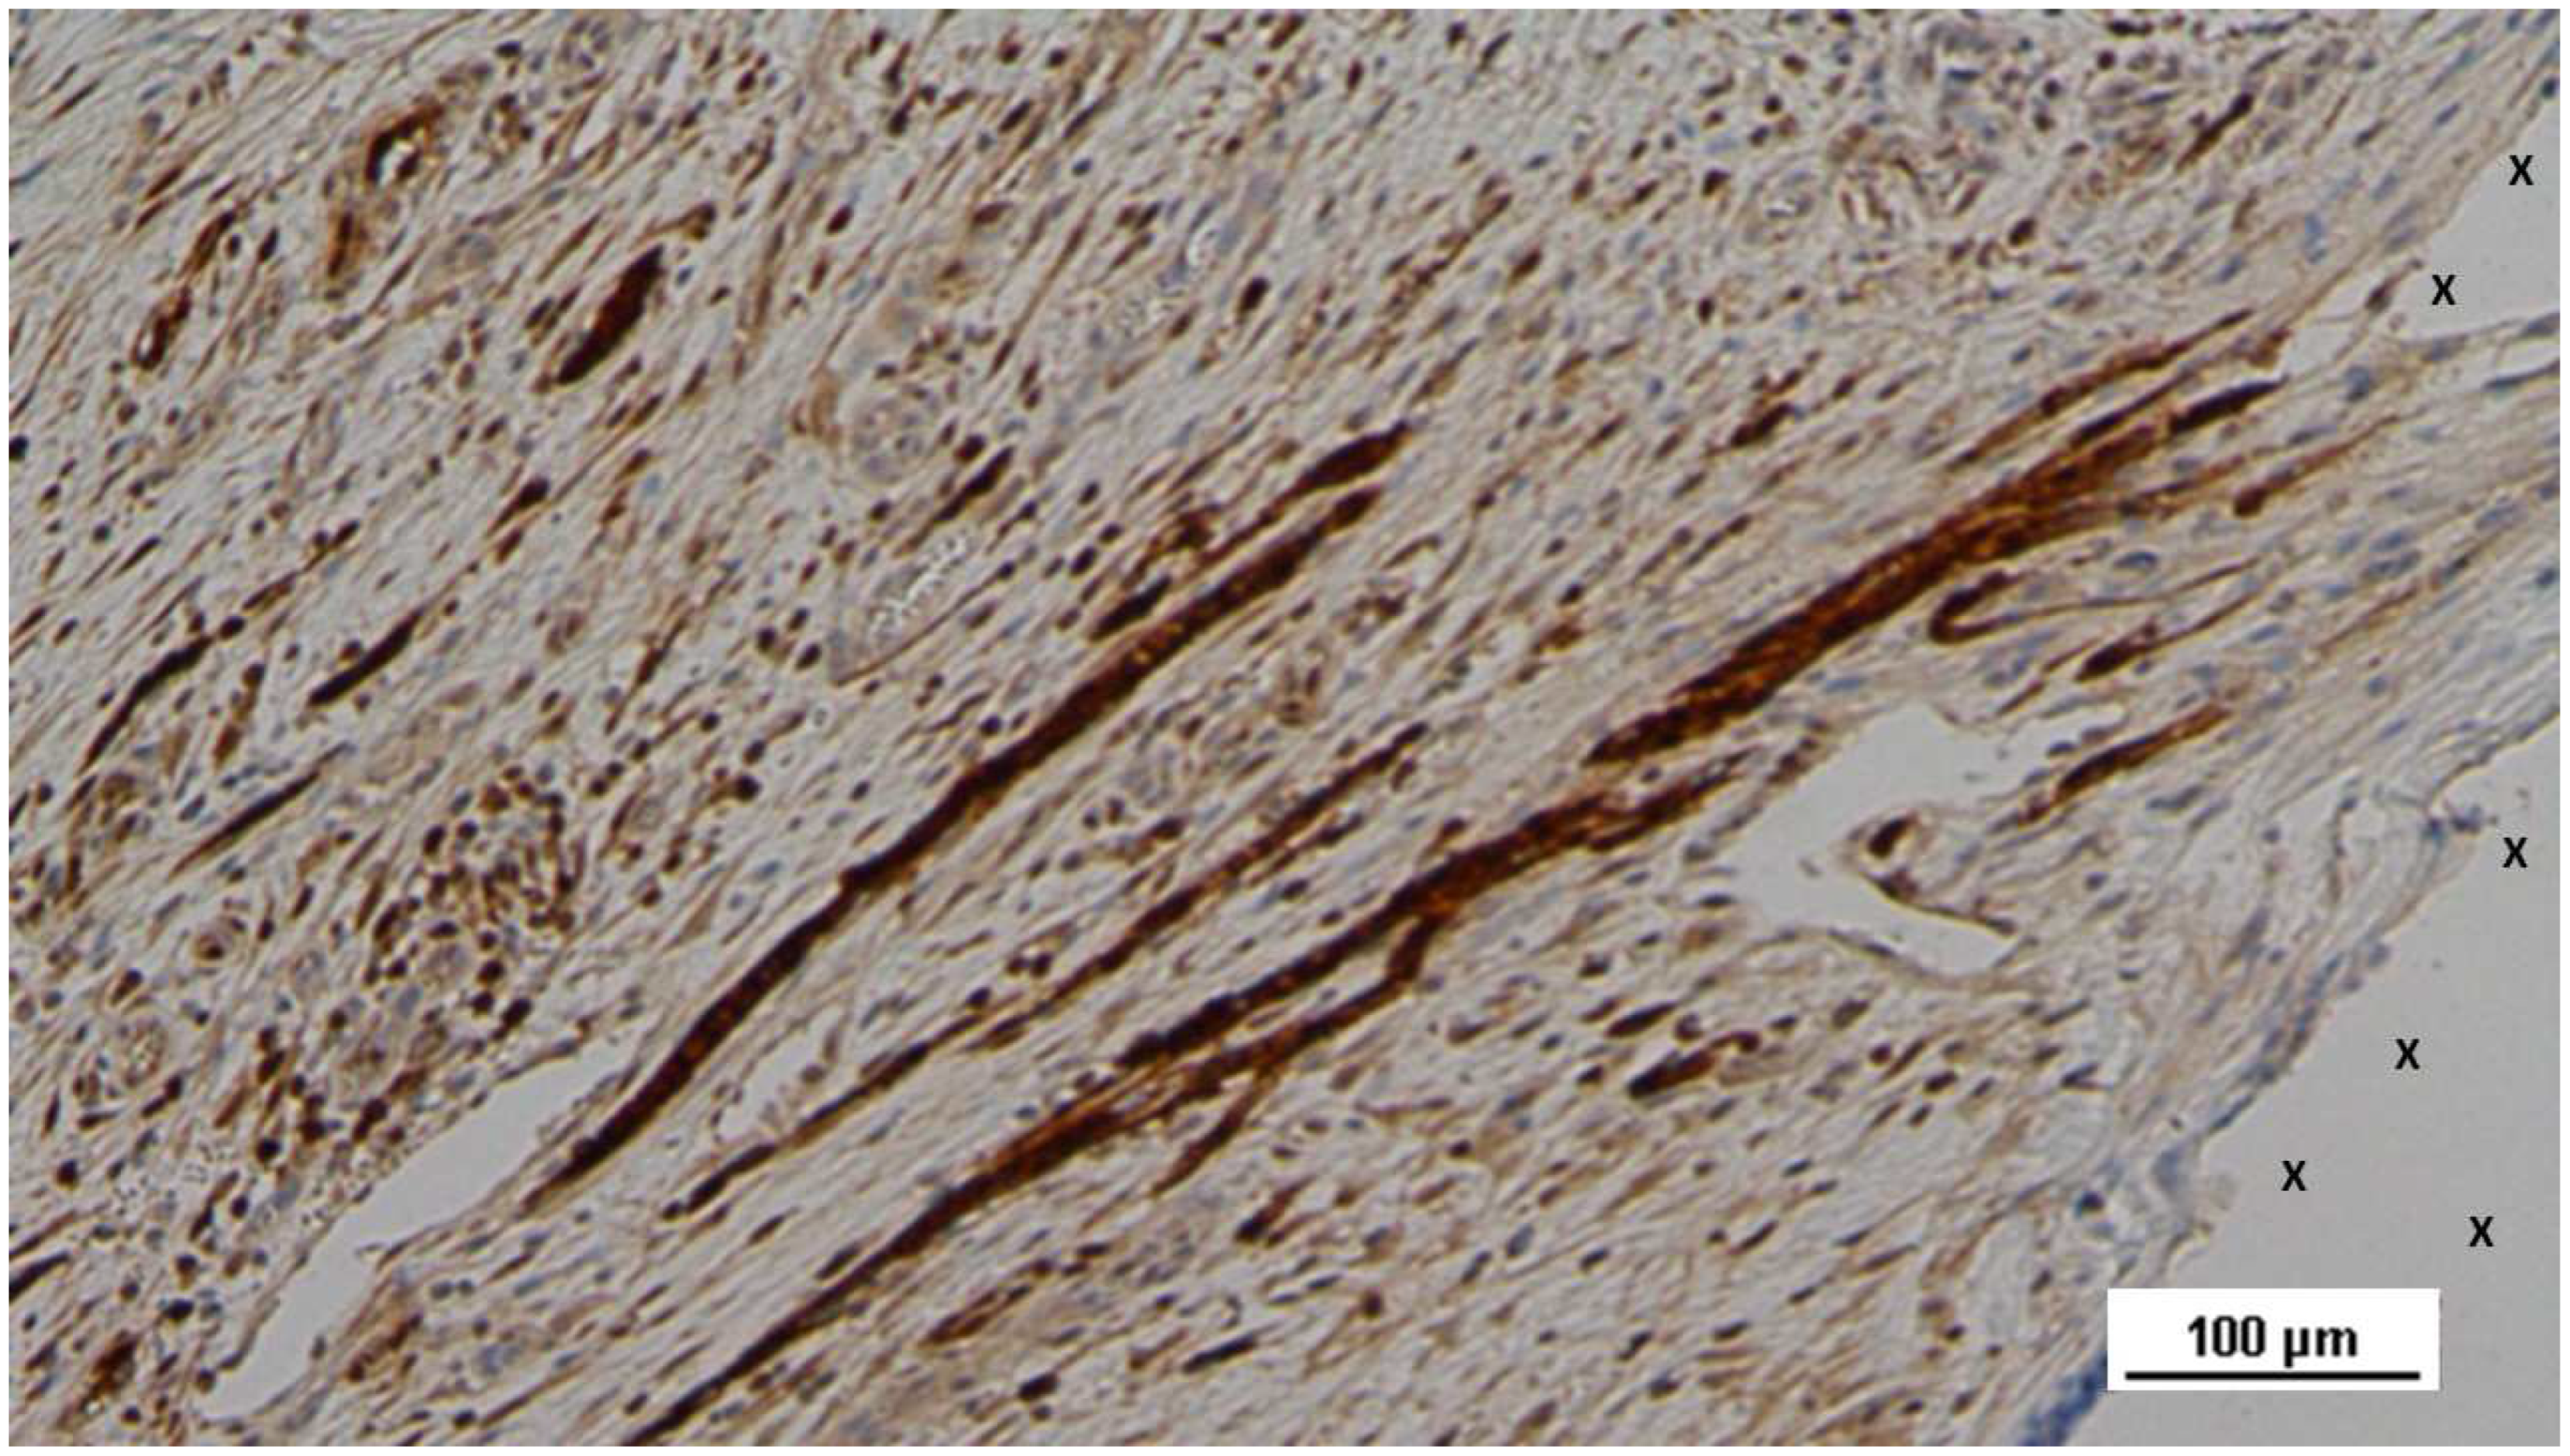

Figure 22. Biopsy specimen excised 4 weeks post-implantation (Short term - ST). Nervous elements (brown staining) in the initial stages of development are present close to the 3D scaffold (X). NSE 100X.

In the early post-implantation period (Short-term, ST), the neurogenic growth factor NGFRp75, which is critical for nerve formation, was observed in limited quantities throughout the S&S Hernia System structure (Figure 21).

During this phase, several immature nerve structures, including developing myelin sheaths, were identified in the scaffold, immersed in well-vascularized connective tissue (Figure 22).